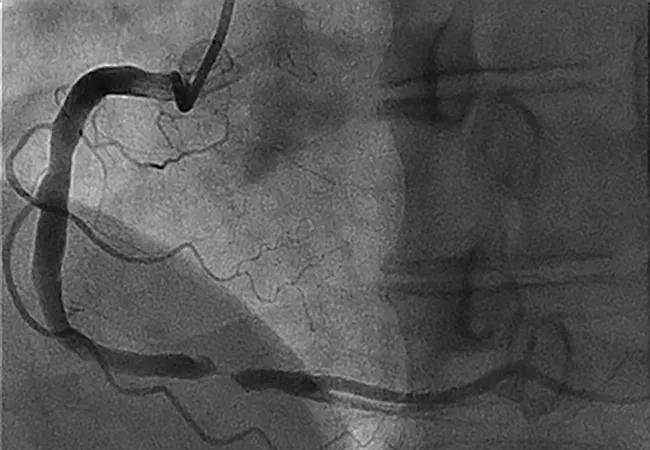

Coronary chronic total occlusion (CTO), defined as TIMI 0 flow for more than three months, is seen on nearly one-third of routine coronary angiograms. Despite the prevailing opinion that CTO is benign, experts in CTO management disagree.

Image at top reprinted, with permission, from Khatri et al., Cleveland Clinic Journal of Medicine (2017;84[suppl 3]:27-38).